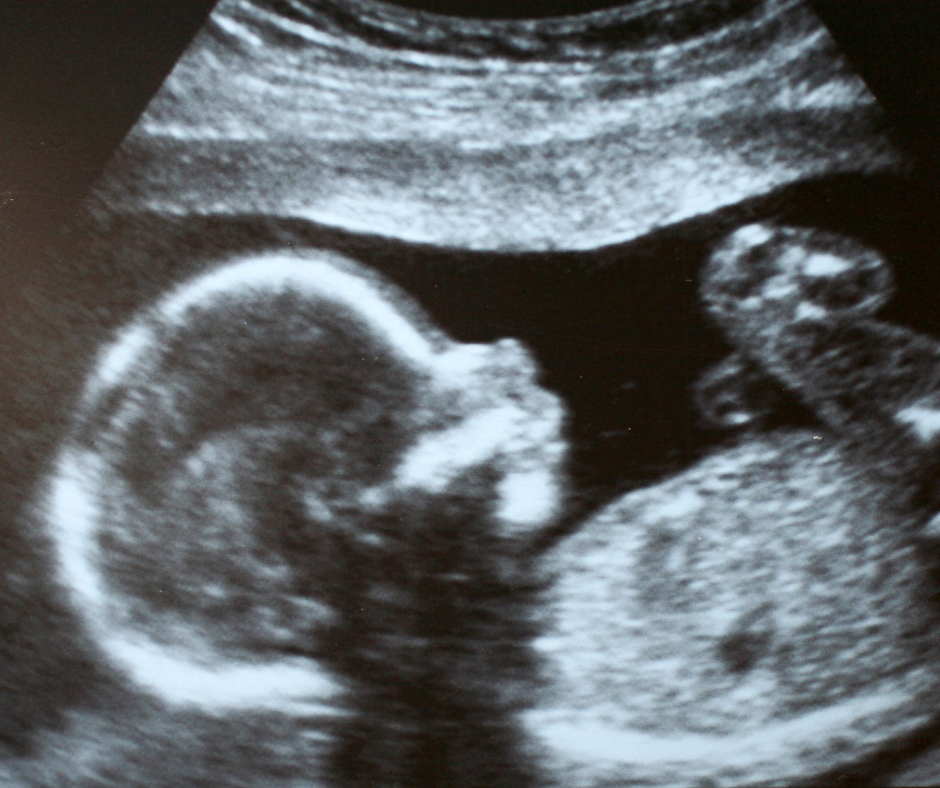

Case Study: When Early Ultrasound Changed the Care Plan

Ultrasound has become an essential tool in modern clinical care—offering real-time insights that can guide safer, more informed decision-making for […]

Ultrasound is becoming an increasingly valuable part of midwifery care, offering midwives real-time insights into fetal development, maternal well-being, and